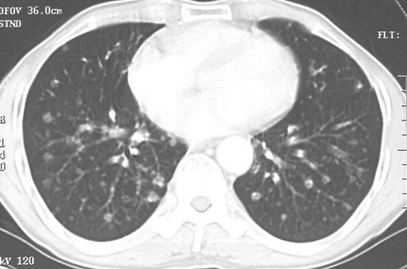

男性,55歲,結(jié)腸癌術(shù)后2年。(本題滿分2.00分)

結(jié)腸癌

A.大葉性肺炎

B.浸潤性肺結(jié)核

C.原發(fā)性肺癌

D.肺轉(zhuǎn)移癌

本題答案:D

題目解析:【該題針對“CT-肺癌”知識點進(jìn)行考核】